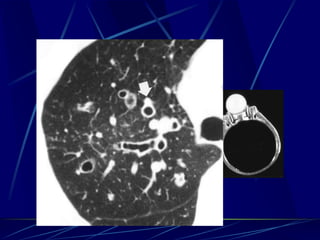

Bronchiectasis

Bronchiectasis is defined as localized bronchial

dilatation. (signet-ring sign)

bronchial wall thickening

lack of normal tapering with visibility of airways

in the peripheral lung

mucus retention in the broncial lumen

associated atelectasis and sometimes air

Signet-Ring Sign

A signet-ring sign represents an axial cut of a dilated bronchus

(ring) with its accompanying small artery (signet).

Tram Tracks

Bronchial dilation with lack of tapering .